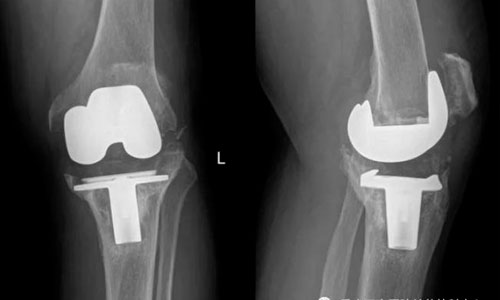

Китайцы напечатали на принтере новый сустав из редкого материала

Впервые в мире китайские ученые использовали технологию трехмерной печати костной ткани для восстановления коленного сустава, передает «Вести.RU». Известно, что сустав, пораженный артритом, меняли 84-летнему пациенту. И в ходе работы применялся редкий металл тантал. При сильных патологических изменениях замена сустава считается наиболее оптимальным вариантом. Однако стандартные протезы приходится подгонять под каждого пациента, что связано с определенными…